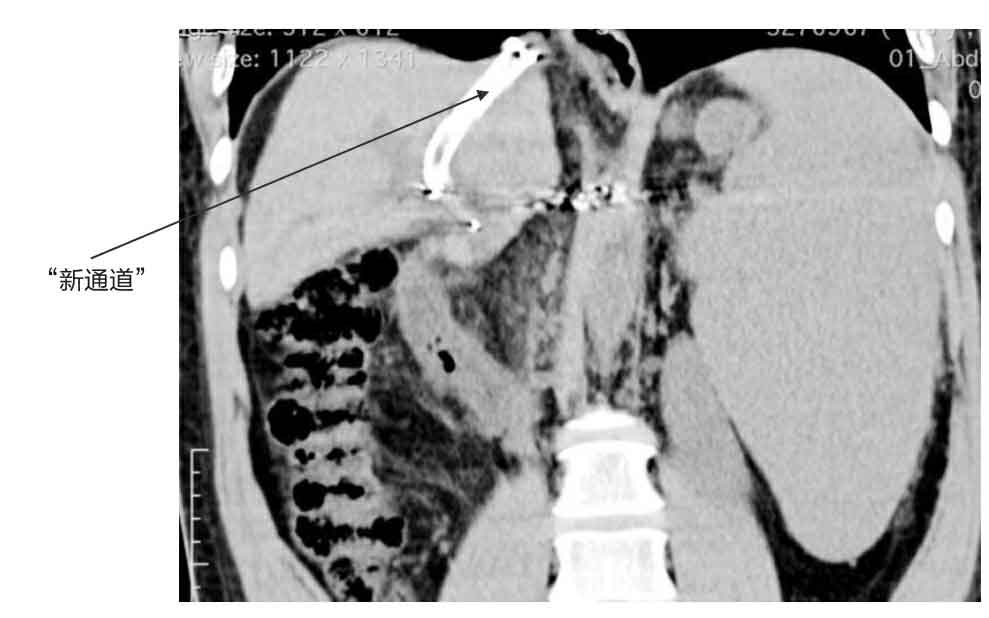

患者CT显示的门静脉和肝静脉之间的“新通道”(图示部分)

此时距离手术开始已经约两个小时了。马上要结束手术了,王大夫又确认了一次引起患者大出血的食管和胃部的静脉血管已经完全止血,门静脉和肝静脉之间的分流道通畅,门静脉降压满意。

TIPS手术成功,患者门静脉压力下降,再次发生大出血的风险大大降低了。这样一来,患者在ICU的后续治疗也相对容易了。我给他应用镇静、镇痛药,让他更安静地度过恢复期;给他应用呼吸机辅助呼吸;继续应用药物维持他的血压;持续监测他的血红蛋白浓度、凝血功能和电解质情况;给他静脉注射肝素避免刚建立的新通道内形成血栓;给他补充白蛋白、应用保肝药……